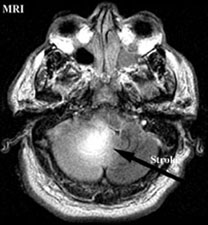

MRI or angiography are adjunct diagnostic methods. Magnetic resonance imaging can be used to create pictures of the brain and can also be used to create pictures of a blood vessel so called MR angiogram (MRA).

By these techniques the doctors can pinpoint the area of stroke in the brain as well as the area of blockage of the vessels.

Flair MR